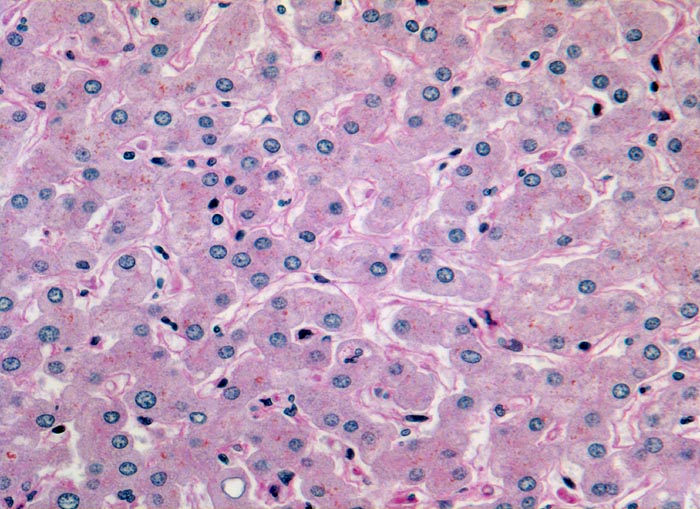

PathoPic ID 3130 - Normales Leberparenchym

Normales Leberparenchym

Normalbefund

Leber

Leber, Gallenwege, Pankreas

Ein- bis zweireihige Leberzellplatten. Dazwischen Sinusoide. In den Sinusoiden sind die Kerne von Endothelzellen und Kupffer'schen Sternzellen erkennbar. Das feinkörnige braune Pigment in den Hepatozyten entspricht Lipofuscinpigment.

Histologie

200